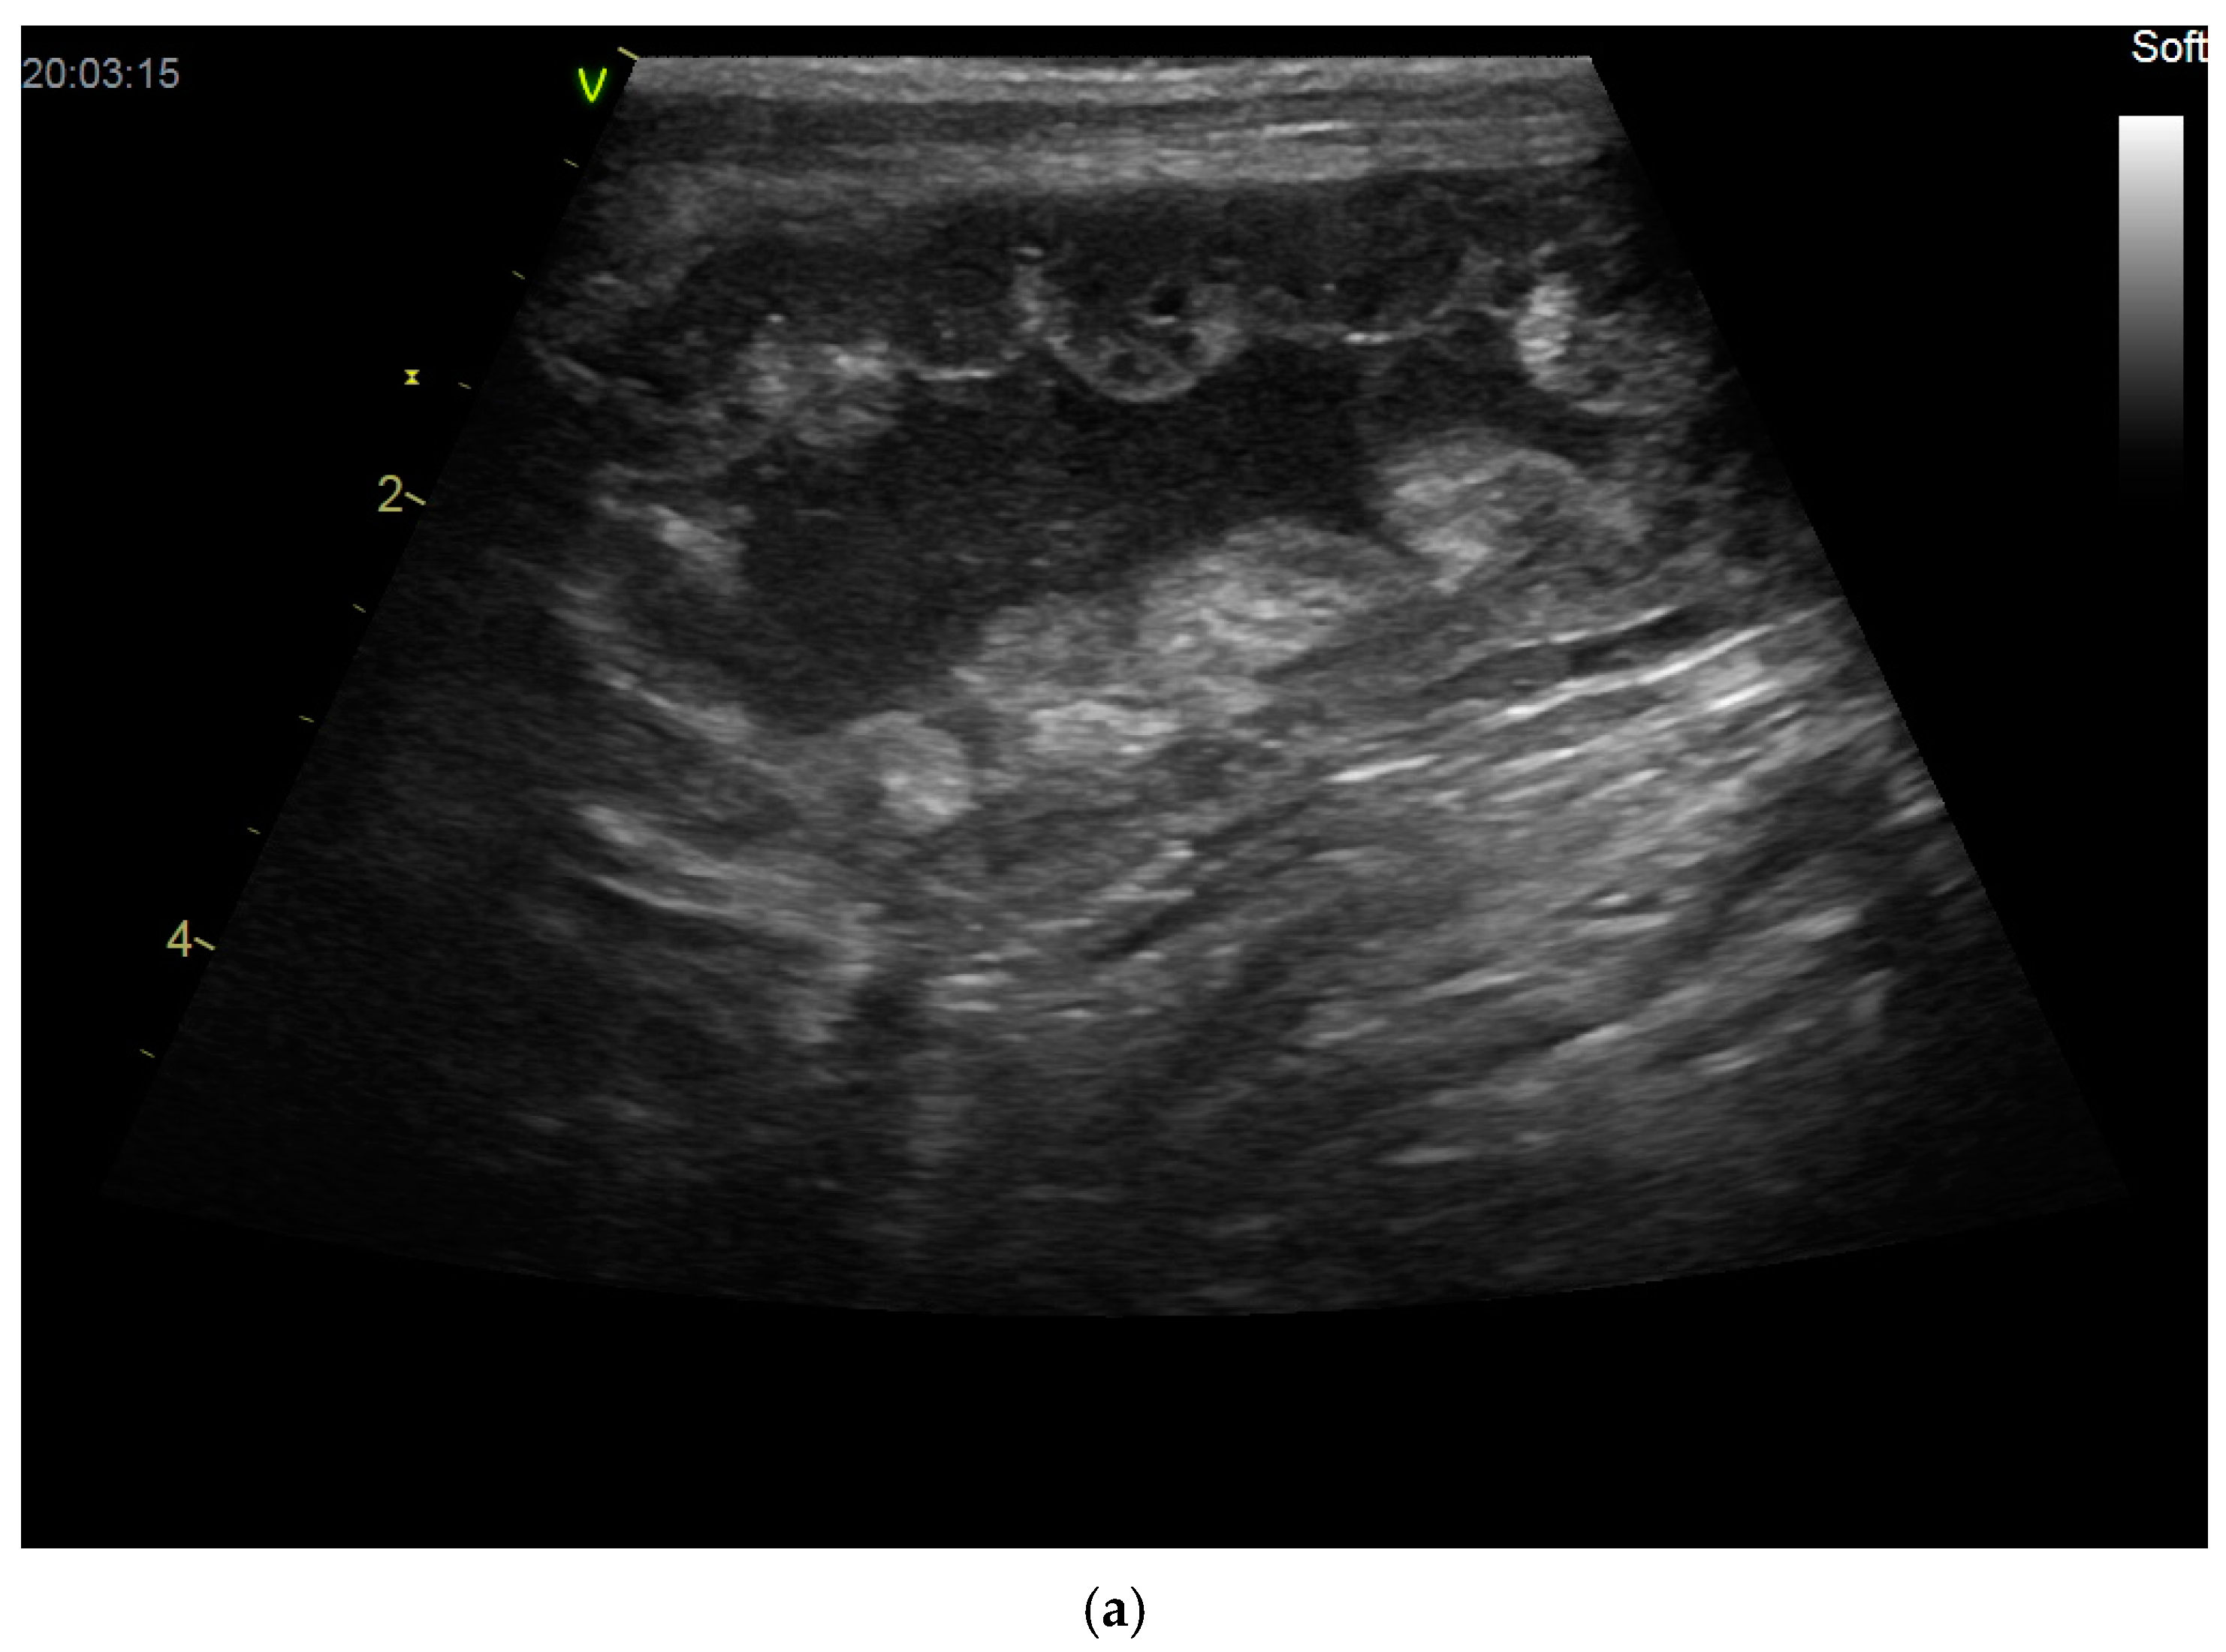

2.3. Uterine Pathology